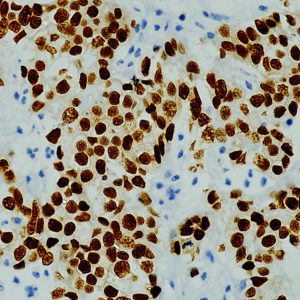

The fluoresceinated Hsa-miR-365A-3P probe has been designed from mature human miR-365A-3P sequence. This Hsa-miR-365A-3P identifies miR-365A-3P sequences in formalin-fixed, paraffin-embedded human tissues and freshly prepared frozen tissues by in situ hybridization. This probe does not react with normal human mRNA or nuclear DNA present in tissues.